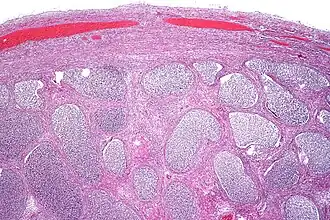

![]() Epididimitis aguda con abundante exudado fibrinopurulento en los túbulos. | ||